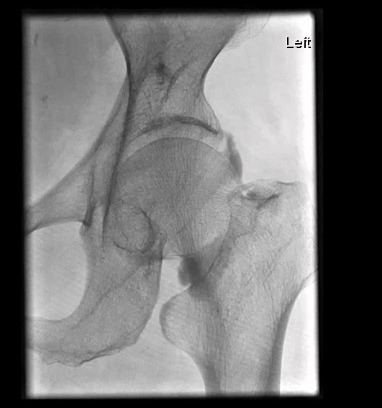

Shoulder pain can be complex with many structures that can generate pain. This includes the bursa, the joint, the rotator cuff tendons and labrum.

Interventions here include bursal injections, joint injections, suprascapular nerve block and suprascapular nerve neurolysis with either RFA or cryoneurolysis.

Embolisation for shoulder pain is also a promising emerging treatment aiming to stop inflammation at its source.